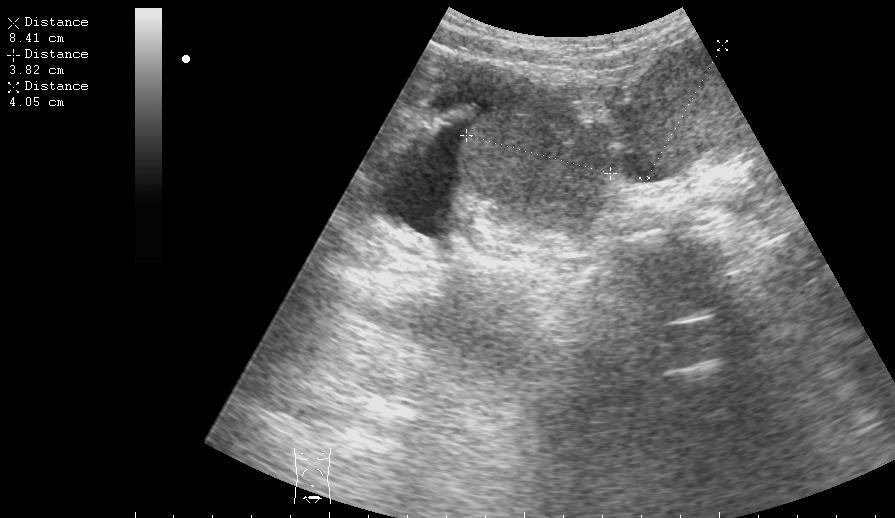

девочка 5 лет, опухоль правого яичника

опухоль правого яичника удалена 3 года назад

Если Это на стороне бывшей операции,то я за рецидив с МТ.Спасибо за бодимаркеры!

первый: малый таз на боку видимо рецидив местный

если то что в брюшной полости не продолжение образования из малого таза....то как вариант mts в брюшине кишечника, в большом сальнике, забр л/у